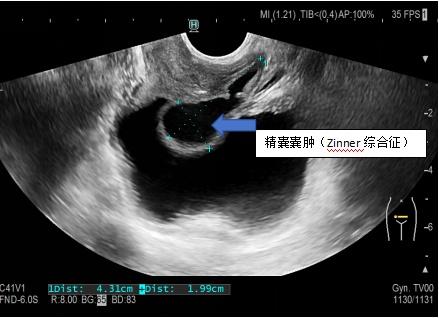

血精是因为前列腺炎吗?"真凶"原来是它